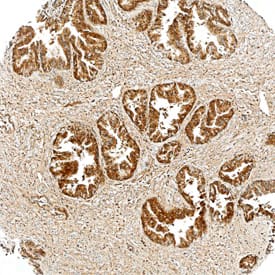

Tensin 4/CTEN antibody in Human Prostate by Immunohistochemistry (IHC-P).

Tensin 4/CTEN in Human Prostate.

Tensin 4/CTEN was detected in immersion fixed paraffin-embedded sections of human prostate using Mouse Anti-Human Tensin 4/ CTEN Monoclonal Antibody (Catalog # MAB6925) at 25 µg/mL overnight at 4 °C. Tissue was stained using the Anti-Mouse HRP-DAB Cell & Tissue Staining Kit (brown; Catalog # CTS002) and counterstained with hematoxylin (blue). Specific staining was localized to cytoplasm in epithelial cells. View our protocol for Chromogenic IHC Staining of Paraffin-embedded Tissue Sections.